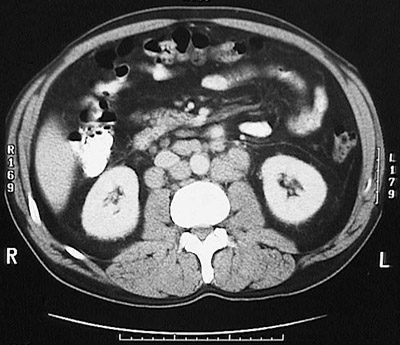

This abdominal CT scan demonstrates prominent periaortic lymphadenopathy involving multiple nodes in a patient with a low grade non-Hodgkin's lymphoma.